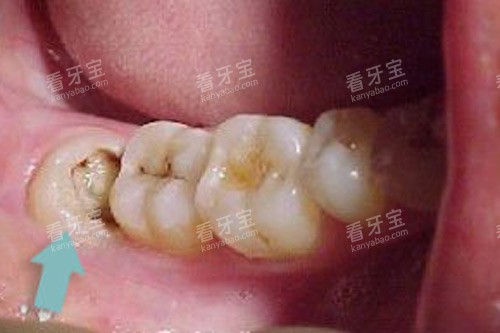

在正式前往拔牙前,我搜集了各类关于智齿的资料。原来智齿又称为第三磨牙,是口腔内比较靠近喉咙的牙齿。由于现代人的颌骨逐渐变窄,智齿经常没有足够的空间正常萌出,从而导致各种问题。我的情况正是如此——右下方的智齿只露出一个小角,大部分被牙龈覆盖,极易藏匿食物残渣,引起冠周炎。

在问询环节,医生详细询问了我的健康状况和药物过敏史,并安排了口腔X光检查。当看到X光片上我那颗倾斜生长的智齿时,医生耐心解释道:“你的这颗智齿属于前倾阻生,牙根形态较为复杂,拔除会有一定难度,但不用太过担心,整个过程都会在麻醉下进行。”